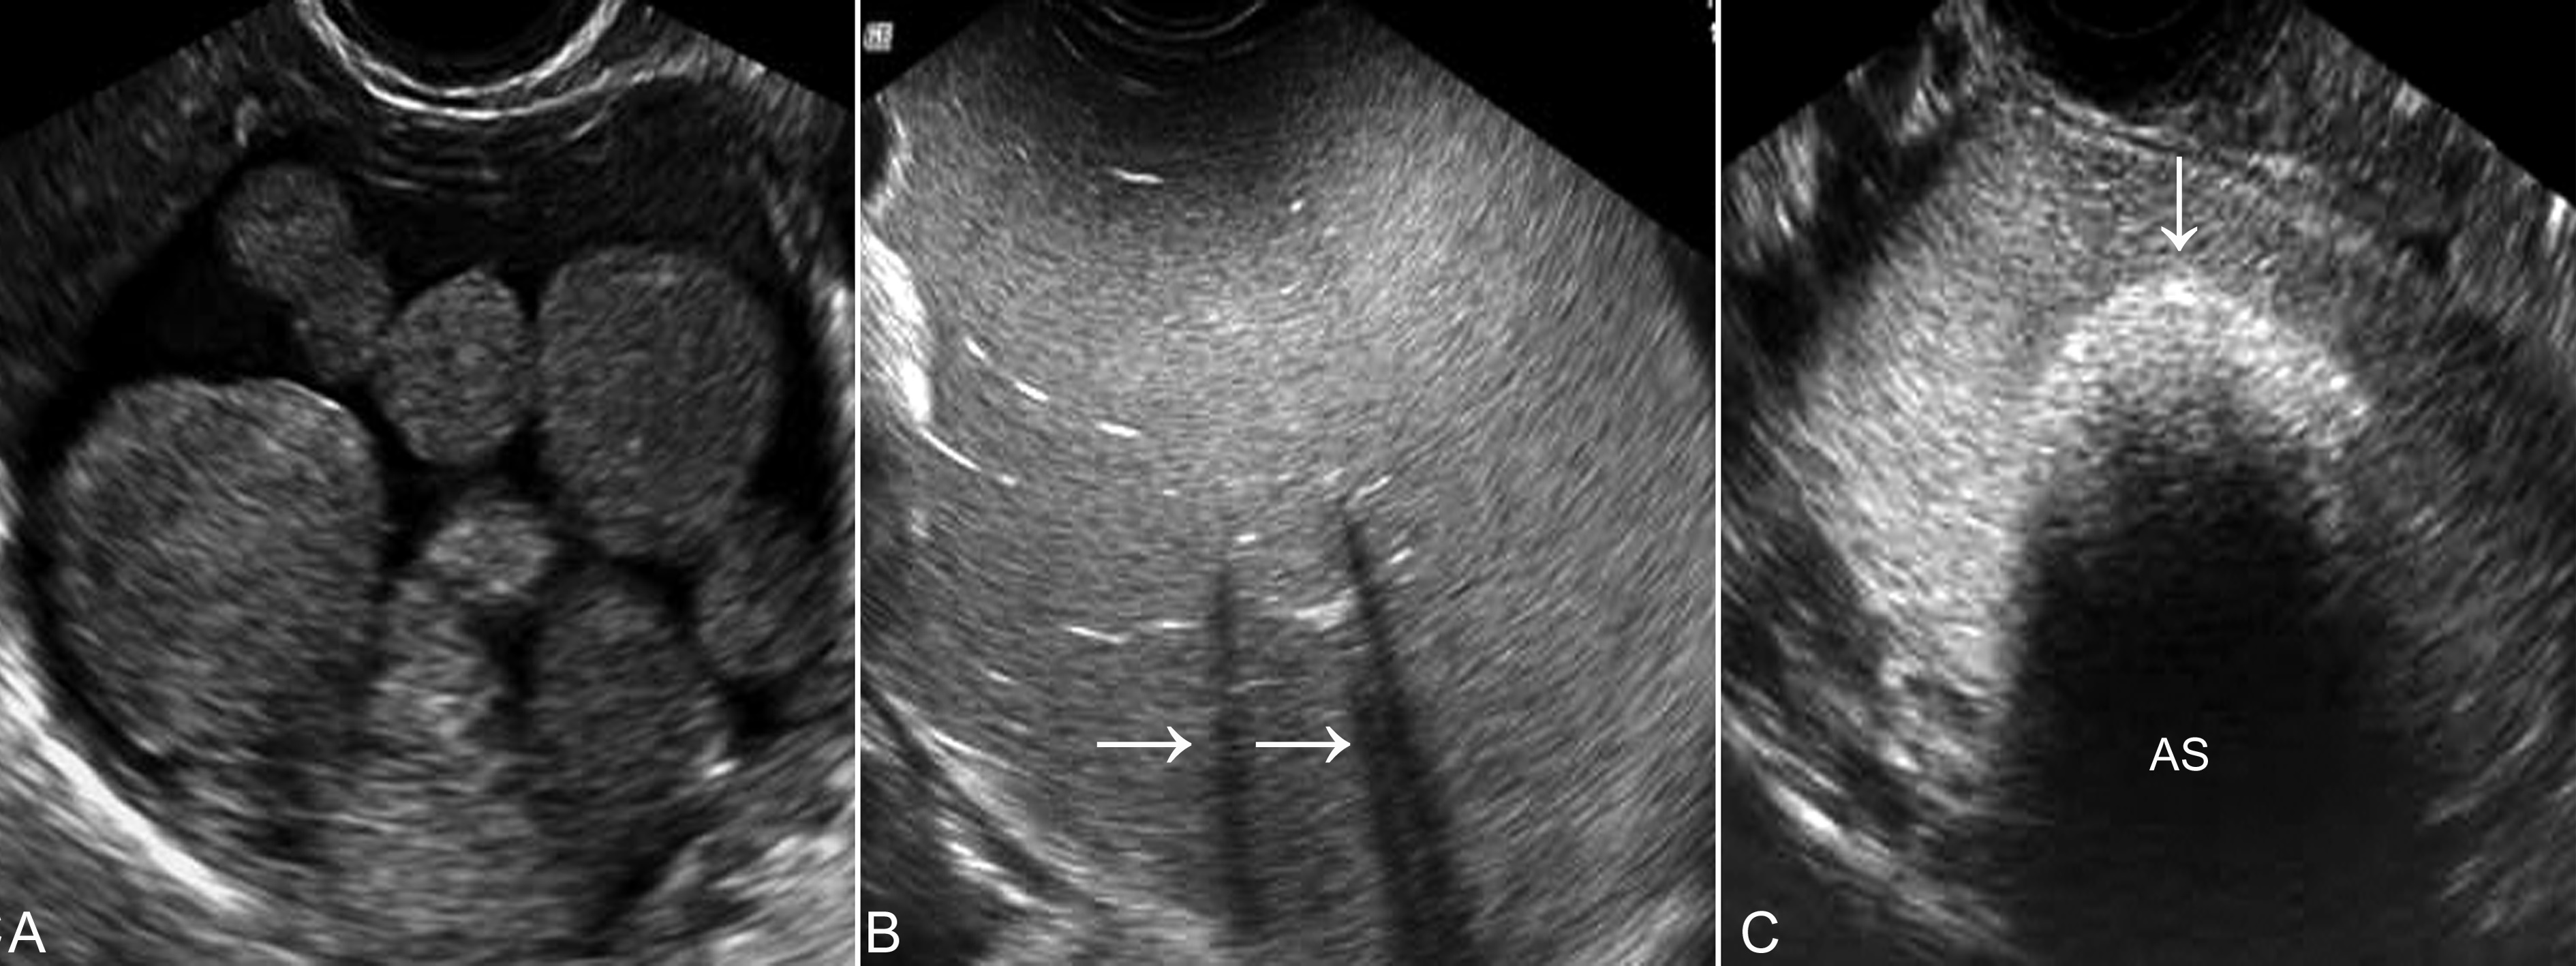

卵巢成熟囊性畸胎瘤(mature cystic teratoma )又称为皮样囊肿(dermoid cyst)。在妊娠期,卵巢成熟囊性畸胎瘤是最常见的卵巢占位性病变,并且也是超声显像检查诊断符合率最高的肿瘤之一,有资料表明,超声显像检查可以显示95%的卵巢畸胎瘤。声像图特点与非妊娠期一样,显示为典型的良性肿瘤回声,形态规则,表面光滑,内部为不均匀的回声区(图1,图1)。以液体为主时内部显示为无回声区,常混有比较强的点状或片状回声,弥漫性分布于无回声区内或沉积于无回声区的下部,随体位移动或振动时可有活动;以有形成份为主时显示较强的不均匀回声,皮脂显示为不甚均匀的强回声,骨骼显示为伴有声影的强回声(图1B),而毛发团则由于声波不能穿透而显示为伴有声尾的强回声(图1C)。

图1卵巢成熟畸胎瘤声像图

A:内部回声不均匀,显示实质性及液体回声共存的特点

B:均匀的回声提示由均匀的皮脂形成,内部混有声影,由骨骼形成

C:伴有声影(AS)的强回声(箭头)由瘤体内的毛发团形成